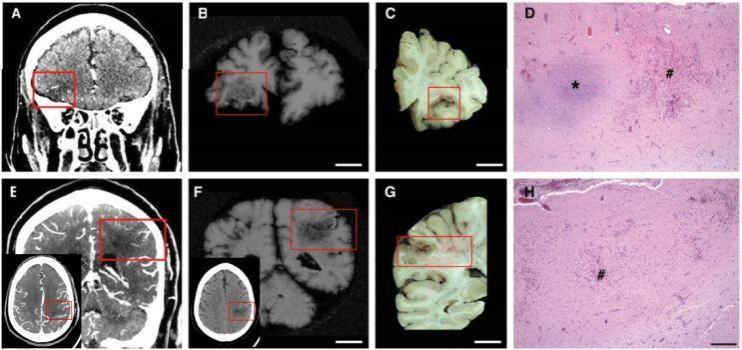

Exhaustive laboratory and clinical investigations had been carried out on all the patients, with some undergoing CT and MRI scans. Interestingly, several of the patients were of Hispanic ethnicity. In order to identify, the presence of the virus in the glia cells and neurons of the brain, the team utilized several methods. These included RT-PCR (a technique to detect viral RNA), RNA in situ hybridization (a method to detect viral RNA inside intact cells), and antibodies test (for the detection of viral proteins within cells).

The brain pathology among the examined patients was distributed into two categories. The first group was those whose brains had suffered damage due to lack of oxygen or Hypoxic damage. "They all had severe lung disease, so it's not surprising that there's hypoxic damage in the brain," explained Dr. Goldman.

In some of the cases the damage—that was caused by strokes—spanned large areas. Most of the damaged areas, however, were very little and were detectable only under a microscope. Comparing it with other features, the researchers suggested hypoxic damage causes to these small areas were brought on blood clots that caused a temporary stoppage of oxygen supply to the said areas.

The second group of patients comprised of those who showed signs of damage to the neurons. Making an unexpected discovery, the researchers found that a large number of microglia had been activated in their brains, and attacked neurons through a process known as neuronophagia.

Microglia are immune cells found in the brain that are activated by pathogens. The activated microglia were mostly found in the lower brain stem (associated with heartbeat and consciousness), and hippocampus (involved in mood and memory).